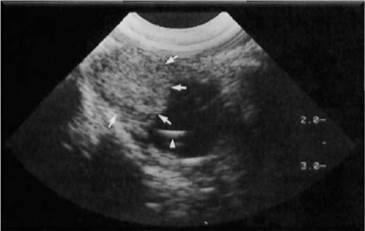

Cuando se habla de ecografía ocular es importante realizar comparación del ojo contra lateral, siempre que sea posible, diferenciando las distintas estructuras oculares como lo son: cornea, cámara anterior, lente (cristalino), cuerpo ciliar, cámara posterior, cámara vítrea, retina y nervio óptico (Figura 9) 10. Además de realizar diferentes cortes: longitudinales, transversales y axiales que permitan diferenciar posibles anormalidades, su ubicación y medida.

Comparando con el caso clínico, y de acuerdo a lo reportado en la bibliografía se puede observar que el ojo izquierdo está ecográficamente normal (Figuras 10 y 11), ya que se identifican todas las estructuras anatómicas normales, sin ningún tipo de alteración.